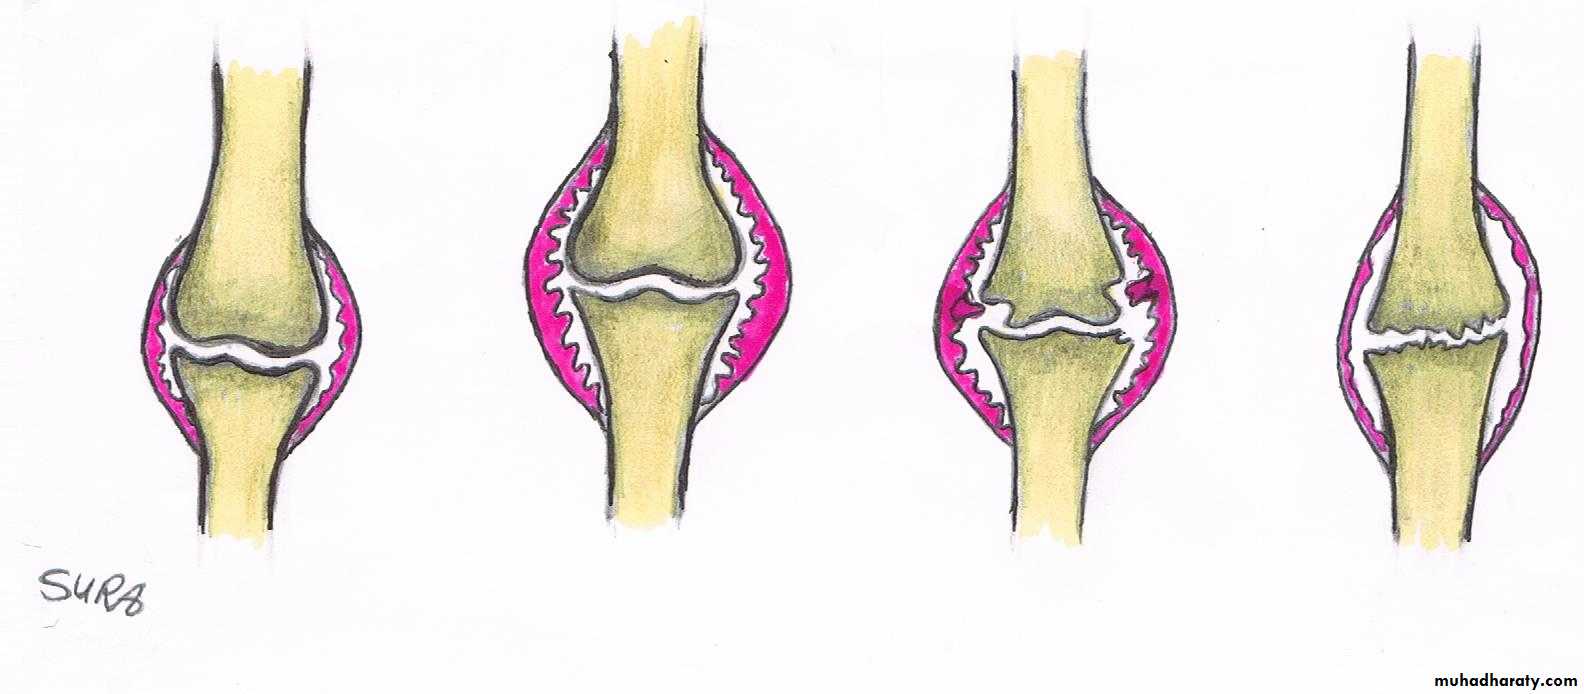

Radiographic features of OA

1- Asymmetric loss of cartilage ( narrowing of joint space).2-Sclerosis of subchondral bone, with subchondral cyst sometimes.

3- Osteophytes (spurring of the joint margins directed toward joint line).